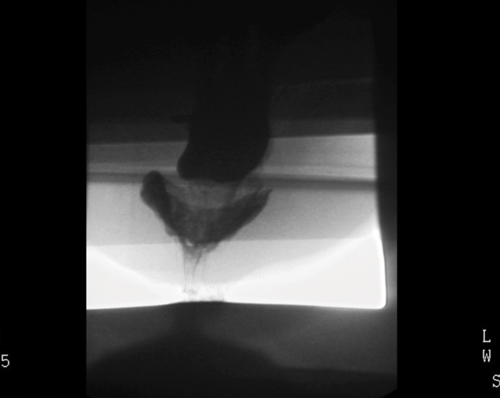

To achieve opacification of small bowel loops in fluoroscopic proctography, approximately 300ml of oral barium suspension is given 45 minutes prior to the beginning of the procedure. This is useful for the diagnosis of possible enterocoele (loops of small bowel in the pelvis). An initial digital rectal examination is performed with the patient in left lateral decubitus position in order to assess the tone of the sphincter complex and to confirm the safety of inserting a rectal tube. Approximately 200-300ml of thick barium paste is injected into the rectum via the tube. The entire examination is recorded through videofluoroscopy. Several video recorded images are obtained in left lateral and in supine positions with the patient responding to requests of ‘squeeze up’, ‘bear down’ and ‘cough’. This is to evaluate the response to increased intra-abdominal pressure. Subsequently, the patient is asked to sit on a specially designed chair and is instructed to empty the rectum completely. This part of the procedure is also video recorded and additionally spot images taken. The whole examination lasts approximately 10-15 minutes. Evaluation of the posterior compartment (rectum) with assessment pelvic floor descent is assisted by using an imaginary line drawn in the lateral views from the pubic bone anteriorly to a fixed segment of coccyx posteriorly (Figure 1).

Figure 1b: Pelvic floor descent with an enterocoele.

Figure 1c: Intussusception on fluoro proctogram.